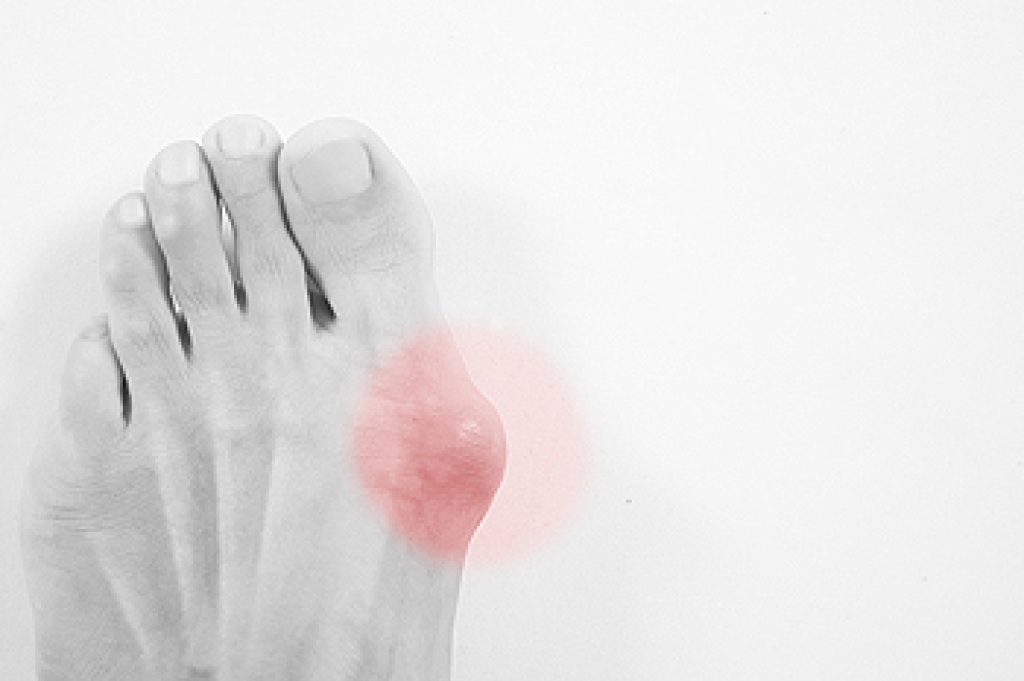

A bony protrusion on the bottom of the big toe may be diagnosed as a bunion. It can occur as a result of genetic factors, or from wearing shoes that do not have adequate room for the toes to move freely in. The medical term for this condition is known as hallux valgus, and it can force the big toe to bend to the side. Some of the symptoms that are often associated with this condition can consist of pain, swelling on or around the affected toe, and arthritis may gradually develop. Moderate relief may be found if a padded bandage is worn over the bunion. This may help to protect it from rubbing against the side of the shoe, and it may be beneficial to refrain from wearing shoes that have a pointed toe area. If you feel you have developed a bunion, it is advised that you speak with a podiatrist who can properly treat this condition.

Bunions are painful bony bumps that usually develop on the inside of the foot at the joint of the big toe. As the deformity increases over time, it may become painful to walk and wear shoes. Women are more likely to exacerbate existing bunions since they often wear tight, narrow shoes that shift their toes together. Bunion pain can be relieved by wearing wider shoes with enough room for the toes.